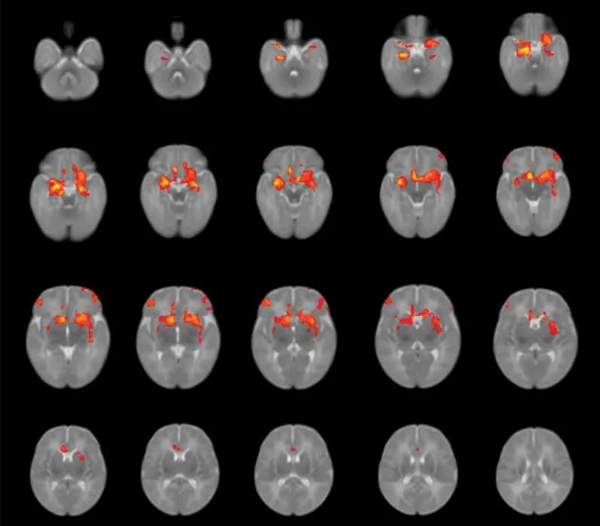

These children, known as the "COVID generation", began to experience unprecedented pressure in the womb. Almost all strangers they saw after birth wore masks. And there could have been more opportunities for friends to play together… Could these changes delay neurodevelopment?

Over the past two years, several small-scale studies has been revealing that the generation born during the epidemic has been affected in many ways, even if they are not infected with the virus.

Researchers compared babies born during the pandemic with pre-pandemic data, they found that these "COVID generation" babies generally scored lower on average on tests of gross motor, fine motor and communication skills. This trend has nothing to do with whether the baby's parents are infected with the COVID, which means that the epidemic environment may be the key problem.

At the same time, the enormous stress the mother experiences during pregnancy may be a major factor that negatively affects the brain development of the fetus.